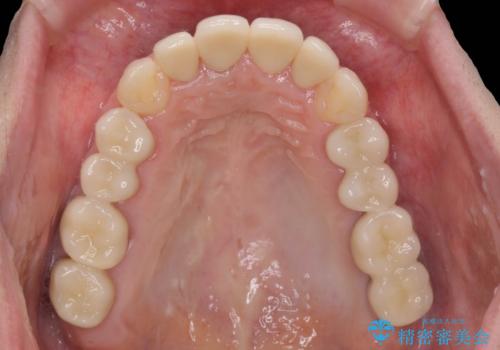

インプラント・セラミック・矯正治療を含む包括歯科診療

- 20代女性

虫歯や咬合関係・歯槽骨の吸収・根尖病変・歯の欠損・複合的な問題を一つずつ解決し、

安定した噛み合わせの構築・歯ブラシのしやすい環境の整備・歯内歯周の感染除去・造骨を伴うインプラント治療

を行い、長期的な予後を見込める口腔内環境を確立、整備して行きます。

セラミック治療の注意事項(リスク・副作用など)

- 天然歯を削ります

- 硬い素材は天然歯を傷つけてしまう場合があります

- かみ合わせや歯ぎしりが強すぎる方はセラミックが割れてしまう可能性があります

- 自費診療(保険適用外治療)となります